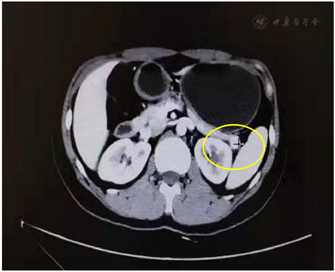

影像检查:颈部超声:右侧甲状腺背部实质性肿块。胸部CT:右肺下叶多发微小结节。腹部增强CT:胰腺尾部结节,结合病史考虑功能性腺瘤;双肾旋转不良,左侧为甚;回盲部多发稍大淋巴结(图1)。胃镜:反流性食管炎(LA-A),糜烂性胃窦炎。甲状旁腺ECT:右叶甲状腺中上极后部类圆形低密度肿块,提示甲状旁腺腺瘤可能(图2)。心电图、心脏超声、腹部超声均未见异常。

患者腹部增强CT示功能性腺瘤,实验室检查示血钙2.71 mmol/L;颈部超声示右侧颈部甲状腺背部实质性肿块,甲状旁腺ECT提示甲状旁腺腺瘤可能;基因检测结果提示Menin基因突变,MEN1诊断明确。患者及其父亲、妹妹的MEN1基因突变(同一杂合变异),目前发现妹妹血钙及PTH高于正常,但没有不适症状,无低血糖表现。